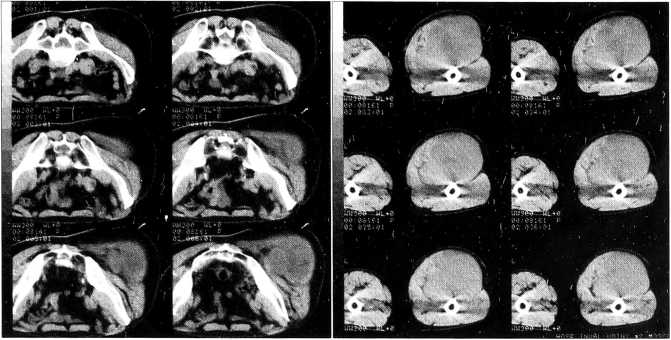

Больной А., 34 лет. Поступил в тяжелом состоянии, с выраженными явлениями интоксикации, расстройствами гемодинамики, нарушениями сознания и зрения. При обследовании определяется огромная опухоль бедра (окружность 104 см) с распадом. Длительное время больной был обездвижен в связи с огромными размерами опухоли. На рентгенограммах правого бедра и голени — опухоль около 50 см в диаметре, неоднородной, ячеистой структуры, с очагами внекостного остеообразования, полостью распада 14x10 см в центре (рис. 3).

Рис. 3. Рентгенограмма больного А. Хондросаркома бедра.

Опухоль разрушает всю нижнюю половину бедренной кости и коленный сустав, ее внекостный компонент достигает верхней трети бедра и средней трети голени по задней поверхности. Диагноз: хондросаркома. Больному произведена компьютерная томография черепа, при которой органической патологии не выявлено. До поступления в нашу клинику больной консультирован в других учреждениях, где ему было отказано в лечении в связи с тяжестью состояния и высоким риском операции.

17.06.99 по срочным показаниям после кратковременной инфузионной подготовки выполнена экзартикуляция бедра. Гистологическое заключение: хондросаркома средней степени зрелости. В послеоперационном периоде после проведенной интенсивной терапии состояние больного улучшилось, отмечено восстановление сознания, зрения, нормализация водно-электролитного баланса и метаболических показателей. Пациент выписан в удовлетворительном состоянии, передвигался с помощью костылей.

Рис. 5. Компьютерная томограмма больного Д. Липосаркома бедра.

Больной Д., 53 лет, на протяжении 15 лет отмечал образование на бедре диаметром около 5 см. В течение 2 лет произошел быстрый рост опухоли. Обратился к онкологу в ноябре 1999 г. При поступлении по задней поверхности правого бедра от подколенной ямки определяется постепенно увеличивающееся вверх и переходящее на правую ягодичную область опухолевидное образование плотно-эластической консистенции, бугристое, безболезненное, размером 50x20 см (рис. 5). В правой подмышечной области имеется плотное образование размером 10x12 см, в левой подмышечной области — образование размером около 3,5 см.